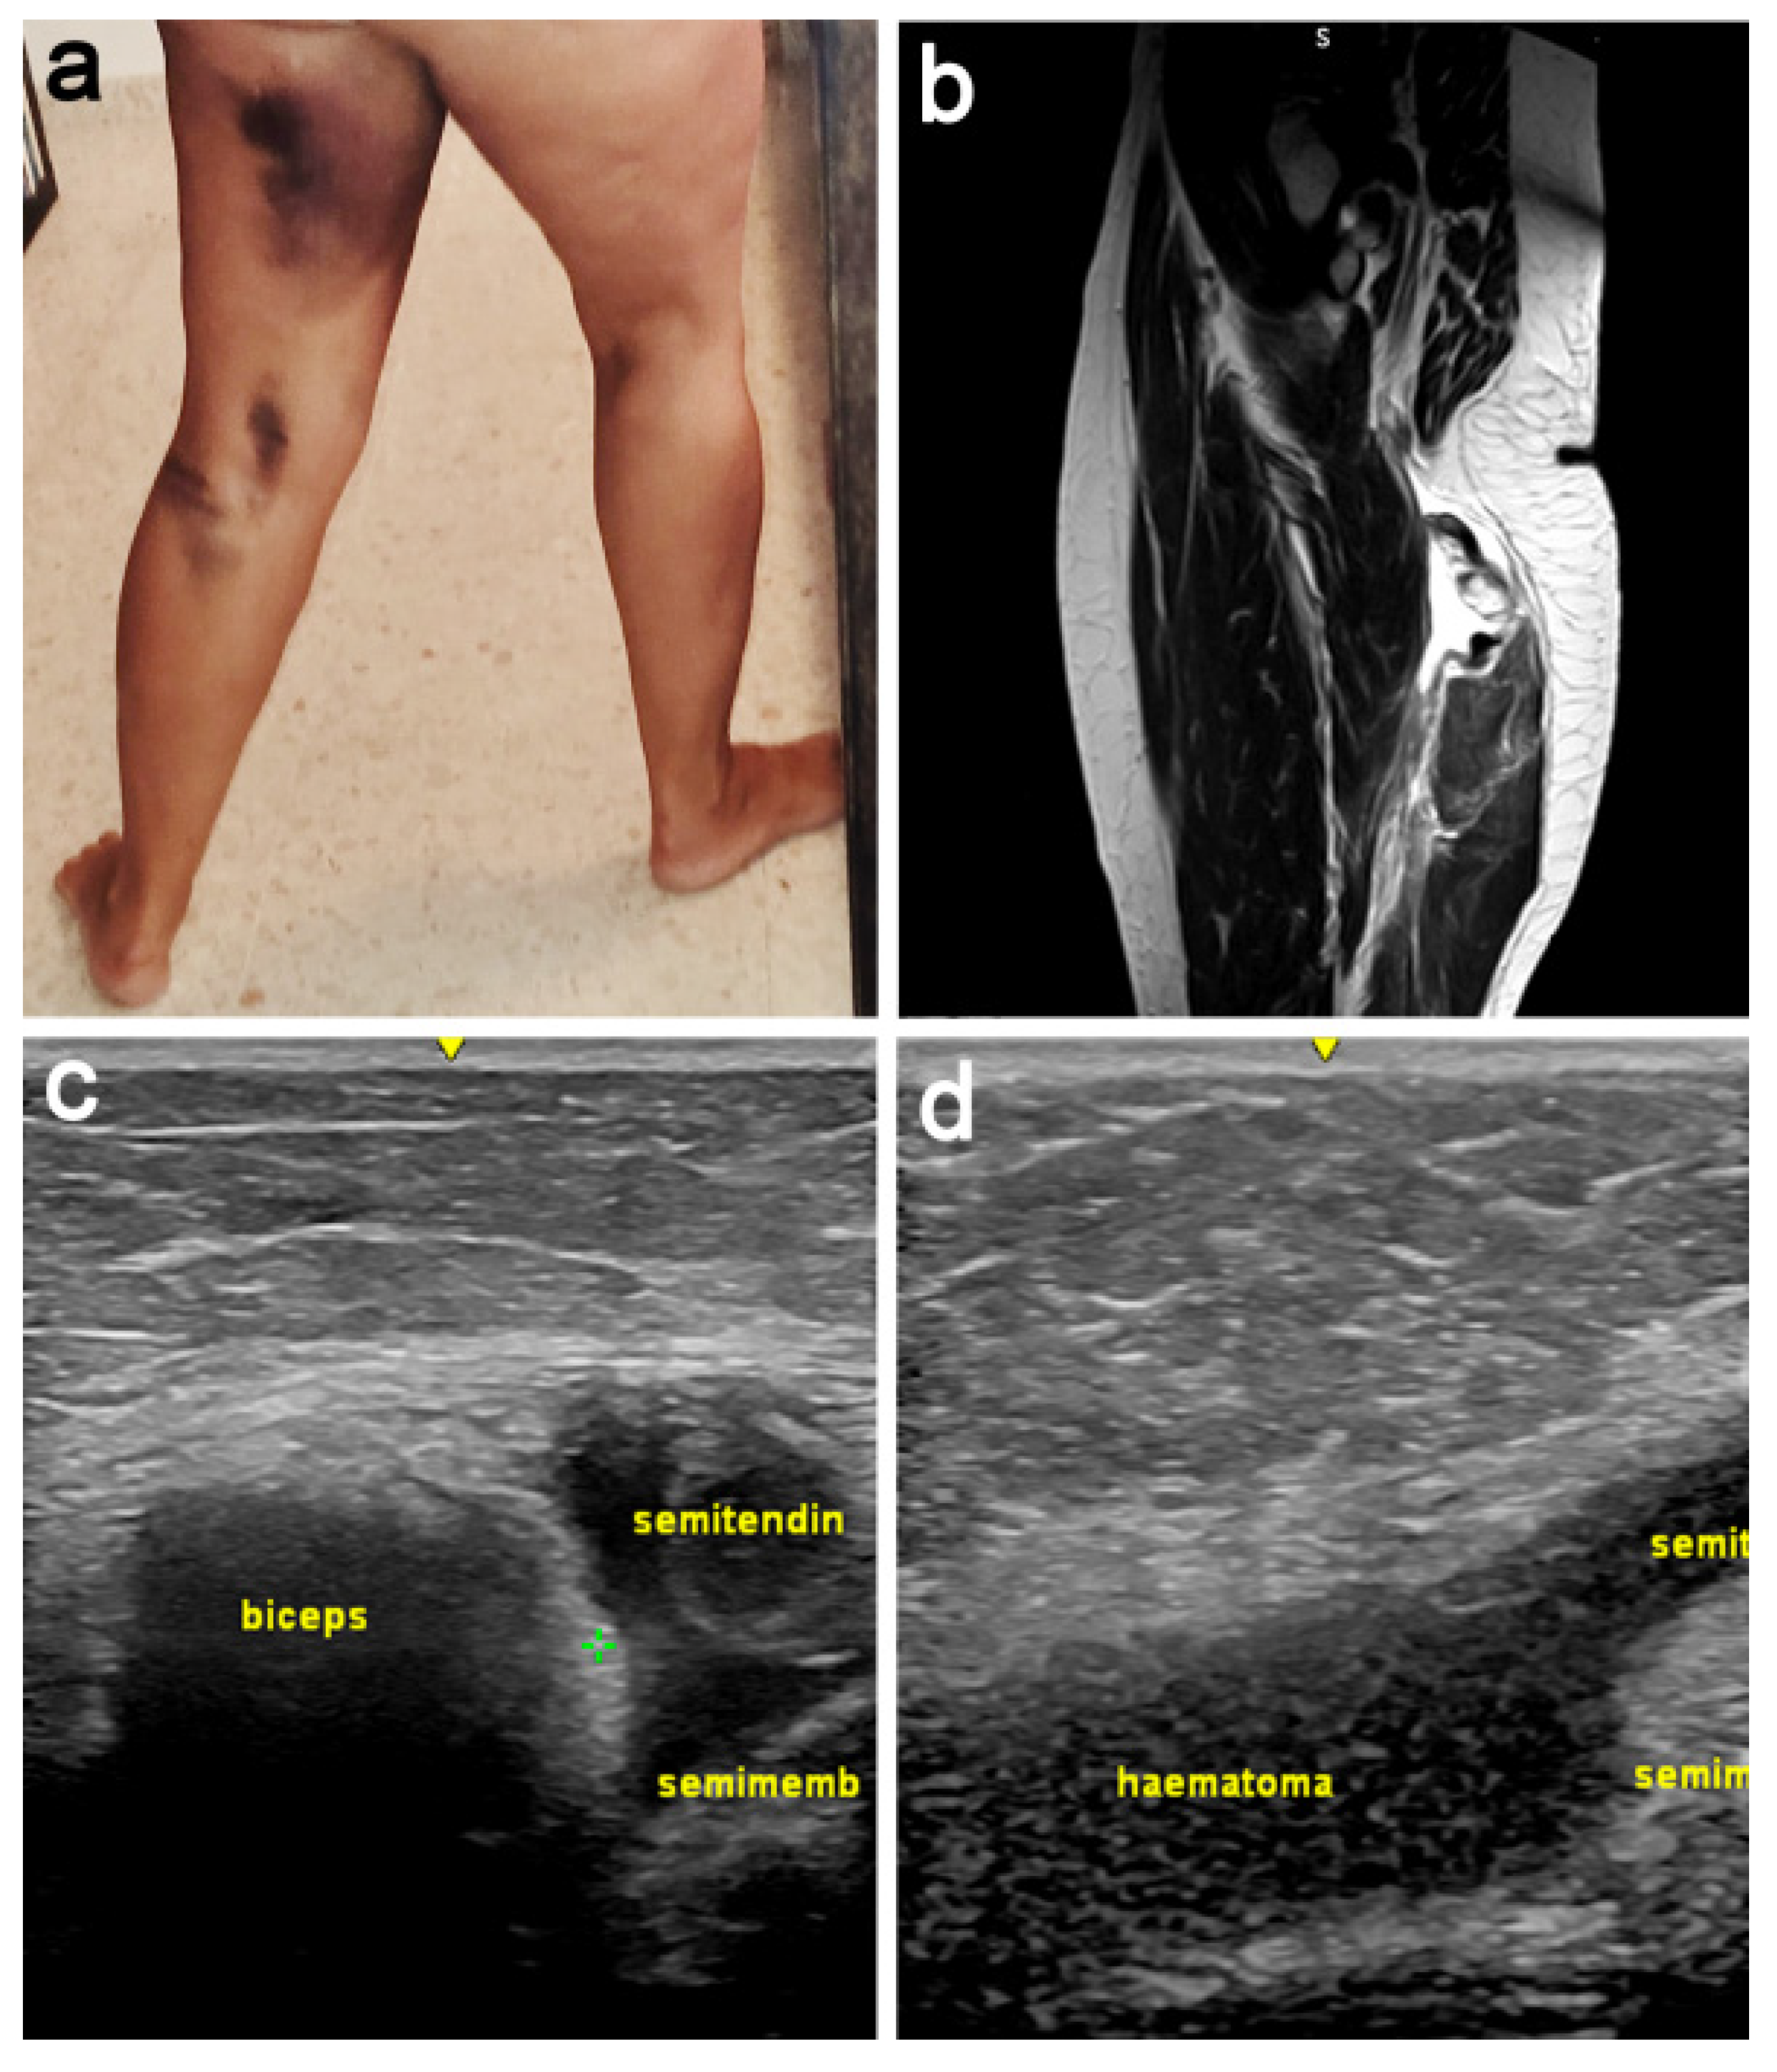

2.1. Patient Presentation and Examination